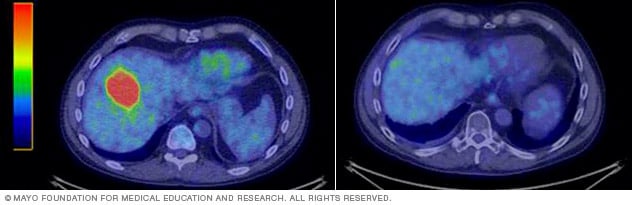

Liver tumor before and after SBRT

Tumor in the liver before (left) and after (right) stereotactic body radiotherapy.

The effects of SBRT happen over a period of time. What happens after treatment depends on the condition being treated and the location of the target. SBRT might result in the following:

- For cancerous targets, the treated tumor may shrink with time, or it may stop growing. Changes are not always seen right away. Early imaging can sometimes show temporary swelling or inflammation related to treatment.